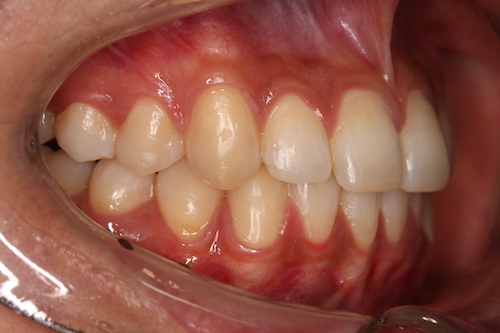

После